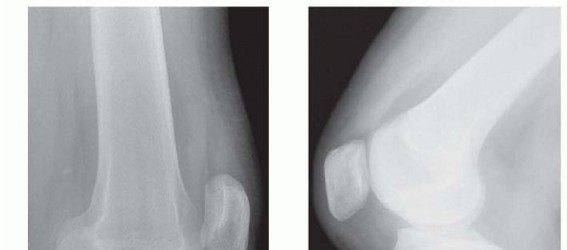

Chapter 40 Arthroscopic Treatment of Elbow Loss of Motion Laith M. Al-Shihabi Chris Mellano Robert W. Wysocki…